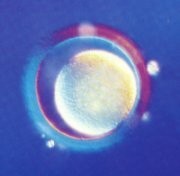

卵子經過大約15釐米長的、狹窄的輸卵管向子宮遊動,它周圍的營養細胞像一串串美麗的光環圍繞著它。很快,它將與精子相遇並開始受精的過程。